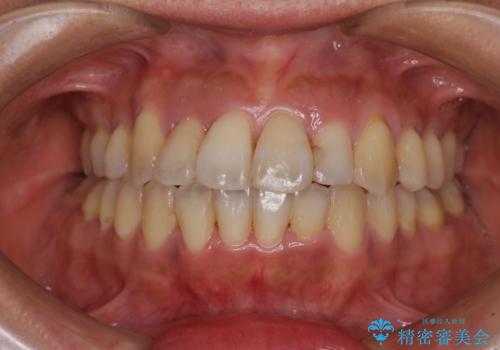

狭い上顎骨を拡大 著しい叢生を抜歯矯正で改善

- 上顎の著しい叢生と奥歯の咬みにくさを気にして来院された患者様です。

骨格的に上顎は狭く、下顎は右側にシフトしていたため、右側臼歯はクロスバイトとなっていました。

上顎骨を急速拡大装置により拡大し、ワイヤー装置による抜歯矯正治療を行うこととしました。

治療途中、長期間海外旅行をされたり、帰国後には遠方へ転居されたりと、治療期間が伸びましたが、2年強で治療を終えることができました。